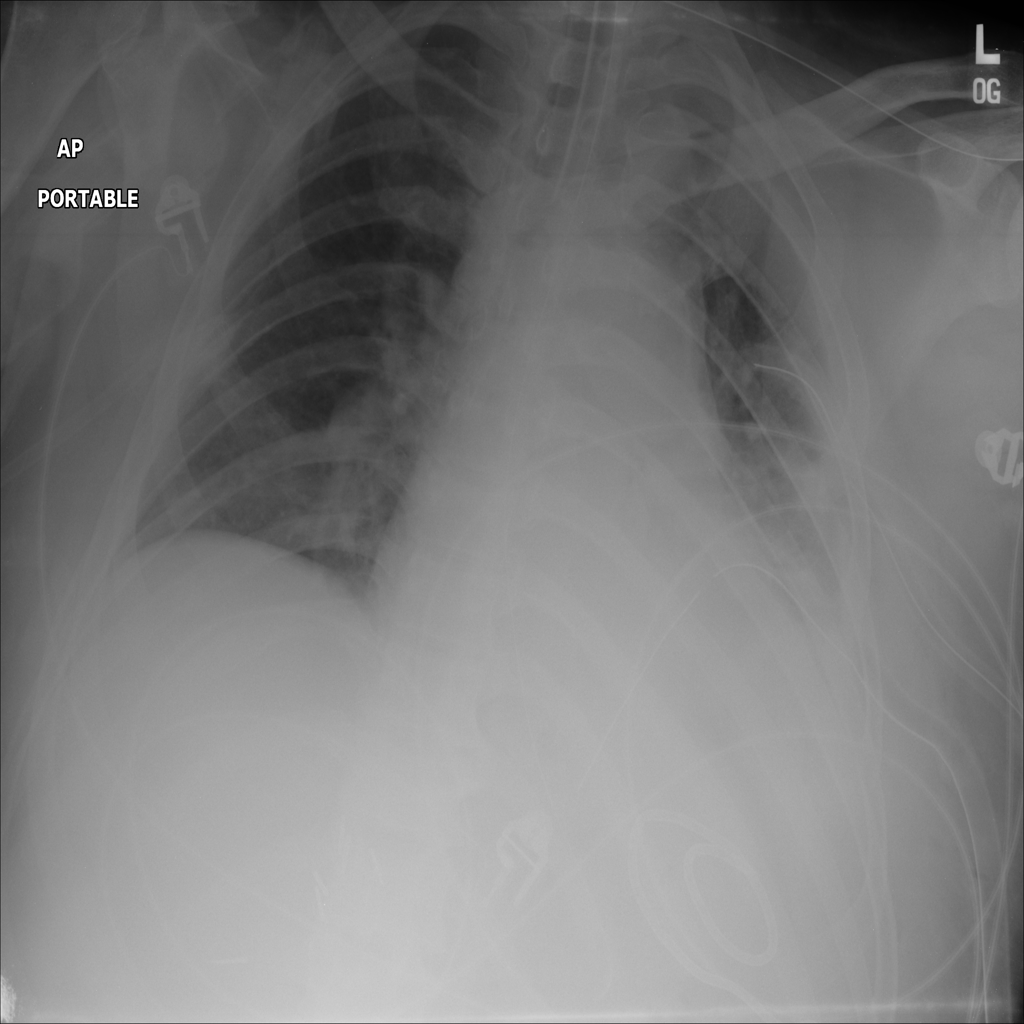

PAT-64EB · IMG-015Consolidation

PAT-64EB · IMG-015

AP